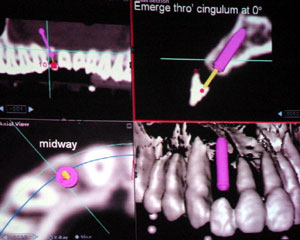

右写真はCT写真から解析したインプラントの理想埋入位置です。

解剖学的形態に則したインプラント位置を決定しています。さらに埋入後、インプラントに正しく人工歯が乗ることが出来る角度も算出しています。これによりかみ合わせの力が正しくインプラントの方向に伝わることが出来るようになっています。

右の写真が術後の写真です。一目見ただけではインプラントがどこに入っているかを見分けることは出来ないでしょう。

右の写真が術後の写真です。一目見ただけではインプラントがどこに入っているかを見分けることは出来ないでしょう。

IGI方式によるインプラントは、様々な解剖学形態を考慮した上で、最適なインプラントが植立出来る方法です。(Case by Dr Ng Fooi Chin, Ko Djeng Gleneagles)